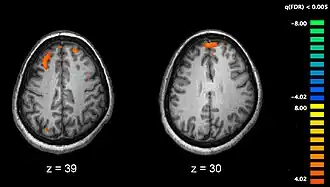

Neurologische factoren

Schizofrenie gaat gepaard met subtiele verschillen in hersenstructuren (in 40 tot 50% van alle gevallen) en in de hersenchemie tijdens acute psychoses. Wetenschappelijk onderzoek waarbij gebruik wordt gemaakt van neuropsychologische tests en neurologische beeldvorming zoals fMRI en PET om functionele verschillen in hersenactiviteiten te bestuderen, heeft uitgewezen dat deze verschillen zich vooral lijken voor te doen in de voorhoofdskwab, de hippocampus en de slaapkwabben. Er zijn gevallen bekend van afname in hersenvolume (minder sterk dan in het geval van de ziekte van Alzheimer) rond de frontale cortex en de slaapkwabben. Het is echter niet zeker of een dergelijke volumeafname progressief is of al bestond voordat de ziekte zich openbaarde. Deze verschillen worden ook wel toegeschreven aan de neurocognitieve stoornissen waarmee schizofrenie vaak gepaard gaat. Aangezien er sprake is van veranderingen in de neurale circuits, wordt ook wel verondersteld dat schizofrenie moet worden beschouwd als een verzameling neurologische ontwikkelingsstoornissen.